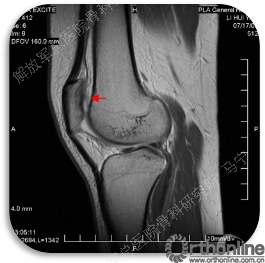

首先经过核磁的检查、评估,初步确定软骨损伤范围,利用T2maping检测序列对软骨的信号区分。图中我们可以看到软骨损伤的范围,并通过计算机计算出大概的面积。

患者右膝疼痛6年,无绞锁,特别是蹲起困难,于2008年住我院,接受关节镜手术,发现股骨滑车局部软骨缺损。

术后8个月修复区的软骨厚度恢复理想,软骨下骨水肿信号不明显。术后16个月复查修复区的软骨没有太明显的变化。